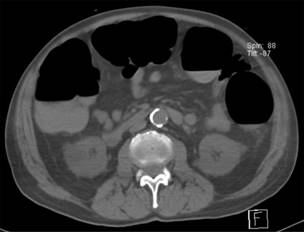

Al cursar el día nueve de ingreso hospitalario, presentó distención abdominal, por lo que se indicó permeabilizar sonda nasogástrica y mantener a derivación, así como el retiro de la nutrición enteral. Tras 48 horas sin presentar mejoría al manejo conservador, y agregándose ausencia de evacuaciones, se solicitó estudio tomográfico abdominopélvico reportando hallazgos en relación con importante dilatación colónica (Figura 1), se solicitó valoración al servicio de cirugía general por los hallazgos tomográficos, resaltando la importancia del diámetro colónico. Y por representar un riesgo incrementado de perforación intestinal se decidió ingresar a quirófano para resolución quirúrgica, se realizó hemicolectomía derecha, colocación de ileostomía tipo Brooke, con un tiempo quirúrgico de cinco horas con los siguientes hallazgos: colon ascendente con incremento de diámetro (12 cm), colon transverso dilatado (8 cm), a nivel de ciego con dilatación importante (9 cm) y pared friable, se excluyó algún fenómeno de obstrucción mecánica en trayecto colónico.

El estudio de imagen ideal sigue siendo la tomografía computarizada (TC) abdominal y pélvica con contraste intravenoso, mostrando una sensibilidad del 96% y una especificidad del 93%. Este método diagnóstico confirma la existencia de una dilatación colónica proximal y excluye otros tipos de obstrucción. La presencia de neumoperitoneo, líquido libre o neumatosis intestinal que se asocie con un colon distendido en la tomografía nos puede llevar a la fuerte sospecha de que se trata de una perforación colónica y esto indica una cirugía de laparotomía urgente.13

Nuestro caso clínico refuerza la asociación a factores de riesgo documentados en la literatura, la pronta sospecha clínica y bioquímica apoyada por el gabinete de imagenología fue pieza fundamental, los hallazgos (Figura 4) en relación a la dilatación colónica brindaron armas suficientes para iniciar el tratamiento farmacológico, teniendo en cuenta el límite superior de diámetro reportado en otros casos con presencia de perforación intestinal, por lo cual la colaboración de un equipo multidisciplinario y la toma de decisiones e intervenciones oportunas incrementaron nuestra tasa de éxito, favoreciendo el pronóstico y desenlace.